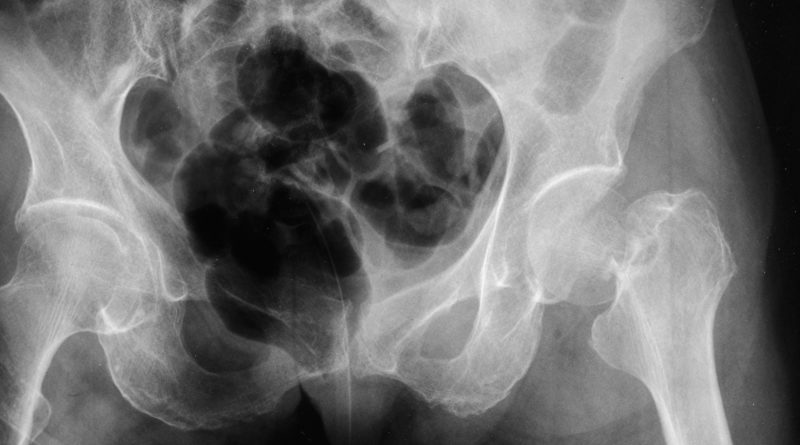

1. Artrite Psoriasica, 6 malattie in una

Antonio Marchesoni, Centro Specialistico Ortopedico Traumatologico Gaetano Pini

Roberto Caporali, Policlinico San Matteo, Pavia